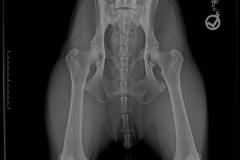

HD ZW: kW25/02 „69“ Größen-ZW: kW25/02 „101!